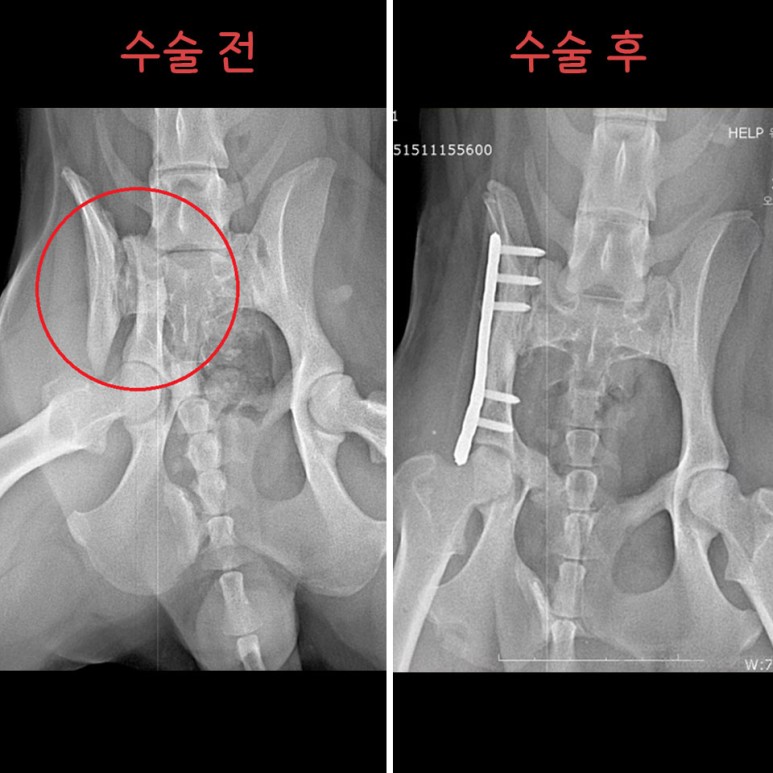

Çüµé! ¿À´ÃÀº '¸Û¼øÀÌ'¶ó´Â °¾ÆÁö¸¦ ¼Ò°³ÇÏ·Á°í ÇØ~! ¸Û¼øÀÌ´Â °³³óÀå ¶áÀå¿¡¼ Å»ÃâÇÑ ¾ÆÀ̾ß. ±ØÀûÀ¸·Î Å»Ãâ ÈÄ ÀÎõ °è¾ç±¸ ÁÖÀ§¸¦ µ¹¾Æ´Ù´Ï´Ù°¡ ±³Åë»ç°í¸¦ ´çÇß´Ù°í ÇÏ´õ¶ó±¸. £¨±×¶§±îÁö ½ÃÀå »óÀÎ ºÐµé¿¡°Ô ¸ÔÀ» °É ¾ò¾î¸ÔÀ¸¸é¼ Áö³Â´Ù°í ÇØ¤Ì¤Ì£© ÀÌÈÄ À¯±â°ß ¼¾ÅÍ¿¡ ÀÔ¼Ò ÈÄ, Áö³ 4¿ù 8ÀÏ ±¸Á¶µÇ¾ú¾î. ±×¸®°í Áö³ 4¿ù 17ÀÏ º´¿ø¿¡ ³»¿øÇØÁÖ¼ÌÂî! ³»¿ø ´ç½Ã ¾ÆÀÌÀÇ »óÅ´ ÀÌ·¯Çß¾î. - ¿ìÃø °ñ¹Ý»ÀÀÇ Àå°ñ³¯°³£¨iliac wing£© °ñÀý - °ñÀýµÈ Áö 1´Þ ÀÌ»ó µÇ¾úÀ¸¸ç, - À§ »çÁø¿¡¼ º¸½Ã´Â °Íó·³, ÃÊ·Ï»öÀ¸·Î Ç¥½ÃÇÑ 1¹øÀÌ È»ìÇ¥ ³¡ºÎºÐ¿¡ ¿¬°áµÇ¾î ÀÖ¾î¾ß ÇØ. - ÇÏÁö¸¸ °ñÀýµÈ Áö ¿À·¡µÇ¾î, ¾ûµ¢ÀÌ ±ÙÀ°ÀÇ À§Ãࣨadaptive shorteningÀÌ ¿¹»óµÇ¾ú¾î£© - ºÎ·¯Áø °ñ¹Ý»À°¡ ±²ÀåÈ÷ °ñ¹Ý ¾ÈÂÊÀ¸·Î µé¾î°¡ ÀÖ°í, - ±ÙÀ°ÀÌ Âª¾ÆÁ® ºÎ·¯Áø »À°¡ ¸Ó¸® ¹æÇâÀ¸·Î ¿Ã¶ó¿Í ÀÖ¾úÁö. µû¶ó¼ ¼ö¼úÀº ÀÌ·¸°Ô ÁøÇàµÇ¾ú¾î. - µÞ´Ù¸® ±ÙÀ° ¹× ¾ûµ¢ÀÌ ±ÙÀ°À» ÀÚ¸£°í Á¥Çô°¡¸ç °ñÀýµÈ ºÎÀ§¿¡ Á¢±ÙÇß°í, - ³»ÃøÀ¸·Î º¯À§µÈ Àå°ñ ³¯°³¸¦ ¹Ù±ùÀ¸·Î ²¨³½ ÈÄ ¿ø·¡ À§Ä¡¿¡ ¸ÂÃçÁÖ¾ú¾î. - °ñÀýµÈ Áö ¿À·¡µÇ¾î, ºÎ·¯Áø »À¿¡ ºÙÀº ±ÙÀ°ÀÌ ½ÉÇÏ°Ô º¯ÇüµÇ¾î ÀÖ¾ú¾î. - µû¶ó¼ ºÎ·¯Áø »À¸¦ ¿ø·¡ À§Ä¡¿¡ ¸ÂÃß´Â µ¥¸¸ 2½Ã°£ ÀÌ»óÀÌ ¼Ò¿äµÇ¾ú¾î. ¼ö¼úÀº ¸Å¿ì Àß µÇ¾úÀ¸¸ç, - ¼ö¼ú ÈÄ¿¡´Â 1ÁÖÀϰ£ ÀÔ¿øÀå »ýȰÀ» Çß¾î. - Åð¿ø ÈÄ 4ÁÖ°£Àº ½Ç³» ÀÚÀ¯ »ýȰÀ» Çϸç, - 2~4ÁÖ¿¡ ÇÑ ¹ø¾¿ X-ray ÃÔ¿µÇÒ ¿¹Á¤À̾ß. - ¿À¸¥ÂÊ ´Ù¸®ÀÇ ¿îµ¿¼º ¹× ¹èº¯Àº Á¤»óÀûÀ¸·Î ÇÏ´ÂÁö ¸ð´ÏÅ͸µÇÒ ¿¹Á¤À̰í! - ±×¸®°í Ç÷¹ÀÌÆ®ÀÇ ±æÀ̰¡ Á¶±Ý ±ä µíÇÏ¿©, 6°³¿ù µÚ Ç÷¹ÀÌÆ® Á¦°ÅÇÒ ¿¹Á¤ÀÌÁö! ±×¸®°í ÀÌ°Ç Åð¿ø Àü ÂïÀº »çÁø! ³Ñ Àß µóÁö!! ¿ì¸® ¸Û¼øÀÌ ³Ñ³Ñ ±âÆ¯ÇØ! ¤Ð¤Ð¤Ð ¸Û¼øÀÌ´Â »ç¶÷¿¡ ´ëÇÑ »óó°¡ ÀÖÀ» ÅÙµ¥µµ, ³Ê¹« ÂøÇØ¼ ´õ´õ¿í ¸¶À½ÀÌ ¾ÆÆÍ¾î ¤Ì¤Ì... Ä¡·á ÈÄ¿¡´Â ±¸Á¶ÀÚ´Ô ´ì¿¡¼ Áö³»¸é¼, ÀÔ¾ç º¸³¾ ¿¹Á¤À̶ó°í ÇØ! ¿ô´Â ¸ð½Àµµ ¿¹»Ú°í ÂøÇØ¼ ²À ÁÁÀº °¡Á·À» ¸¸³¯ °Å¾ß ¸Û¼ø¾Æ! ¸Û¼øÀÌ ³Ê¹«³Ê¹« »ç¶ûÇØ! ³Ê¹«³Ê¹« ±âƯÇϰí ÂøÇÑ ¸Û¼øÀÌ °í¸¶¿ö ¢½ ¢½ °¡Á·ÀÇ Ç°ÀÌ Àý½ÇÇÑ ¸Û¼øÀÌ¿¡°Ô ¸¹Àº °ü½É ºÎÅ¹ÇØ!!! À̸§: ¸Û¼ø £¨¿©¾Æ, Áß¼ºÈ ¿Ï·á£© ³ªÀÌ: 1¼¼ Ư±â: ÇØ¸¼Àº ¿ôÀ½¢¾